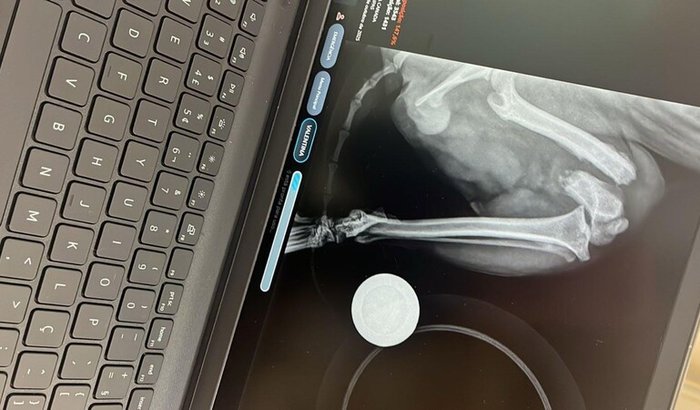

A minha princesa fez 1 ano esse mês de Outubro, tudo estava indo bem, até ela cair e o diagnóstico pelo raio x ser desesperador.

Ela precisa operar o quanto antes, antes que evolua pra uma infecção ou algo bem pior, como por exemplo uma amputação.